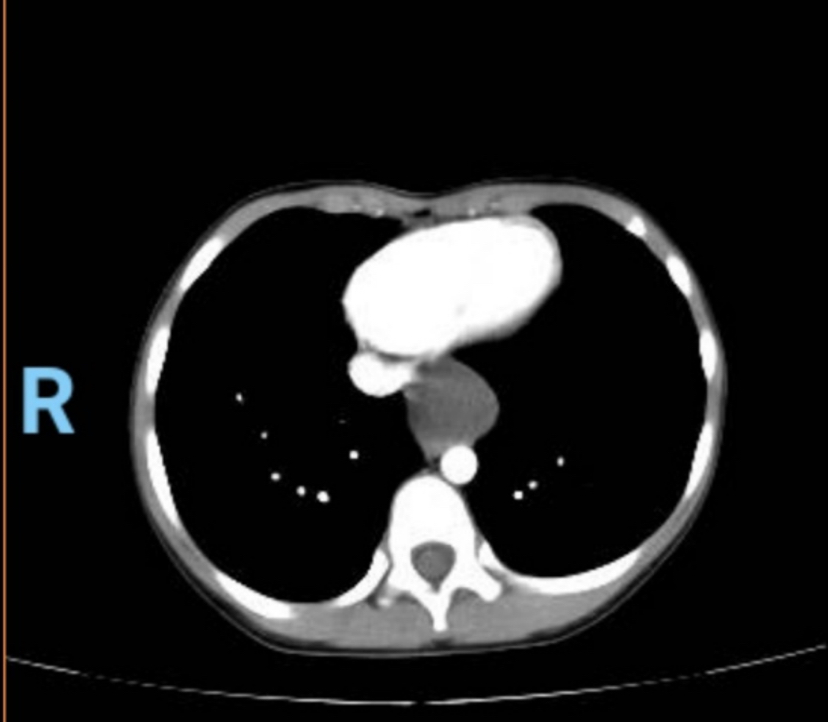

7岁女孩小优优还在妈妈肚子里的时候就被医生发现她的胸腔里长了颗“小豌豆”,诊断是后纵隔占位,从优优出生开始,这颗“小豌豆”也在她身体里悄悄地生长着。优优最开始倒是没有明显的不舒服,与其他小朋友一样,觉睡得好,饭也吃得香,优优妈妈看她健康活泼,也不想孩子小小年纪就被推进手术室,怕给她留下心理阴影,就没去做手术。一段时间过去,优优吃饭吞咽时总感到有些阻碍,今年年初优优妈妈带她复查,发现优优那颗纵隔肿瘤近年来逐渐增大,已长大到5*6厘米,柠檬大小,位于心脏后方,跨越左右胸腔和部分腹膜后,与食道关系密切,压迫了食管,使得食管变窄,情况不好,唯一的出路就是手术切除。

复查结果令优优妈妈很担忧,2个月前的一个周三下午,优优妈妈带着优优来到了深圳市人民医院名医门诊,找到王光锁教授,为小优优量身定制个体化手术方案。手术时机不宜继续推迟,可以考虑切除了。但要怎么做呢?怎样才能以最小的代价、最小的创伤,精准地切除潜伏在后纵隔狭窄间隙里、跨越左右胸腔和胸腹腔的肿瘤呢?

年幼的小优优胸腔狭小,肿瘤又位于后纵隔狭窄间隙,这是手术机器人的优势所在。上世纪90年代末,时任深圳市人民医院胸外科主任的王正率先在国内推动小儿胸腔镜技术,得到包括裘法祖院士在内的外科专家的肯定,小儿胸外科麻醉也积累了丰富的经验。